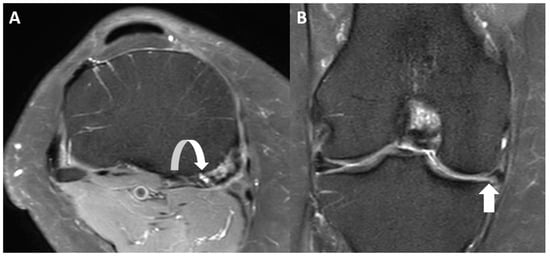

2.4. Qualitative Image Analysis